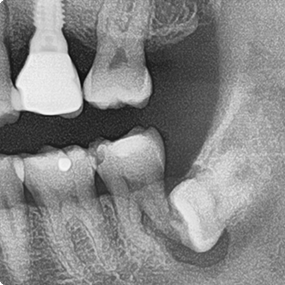

☆本院特別巨資增設 ”千萬級3D AI透視電腦斷層”,並配合“成骨膠原蛋白”施作 (上述兩項目前健保無給付),讓您遠離神經傷害、口鼻竇(炎)相通...等併發症,除健保之外,難免會有避免併發症風險的自費項目,網路上經常會有看到智齒拔完後唇麻、舌麻、口鼻竇相通等併發症,在本院嚴格自我要求下,此類併發症在本院幾乎趨近於零。

(兩條紅線中間黑色區域即為神經管)

外面拔完時常術後唇麻舌麻,本院發生趨近於零